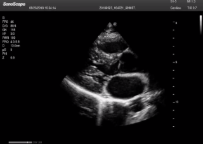

四腔心